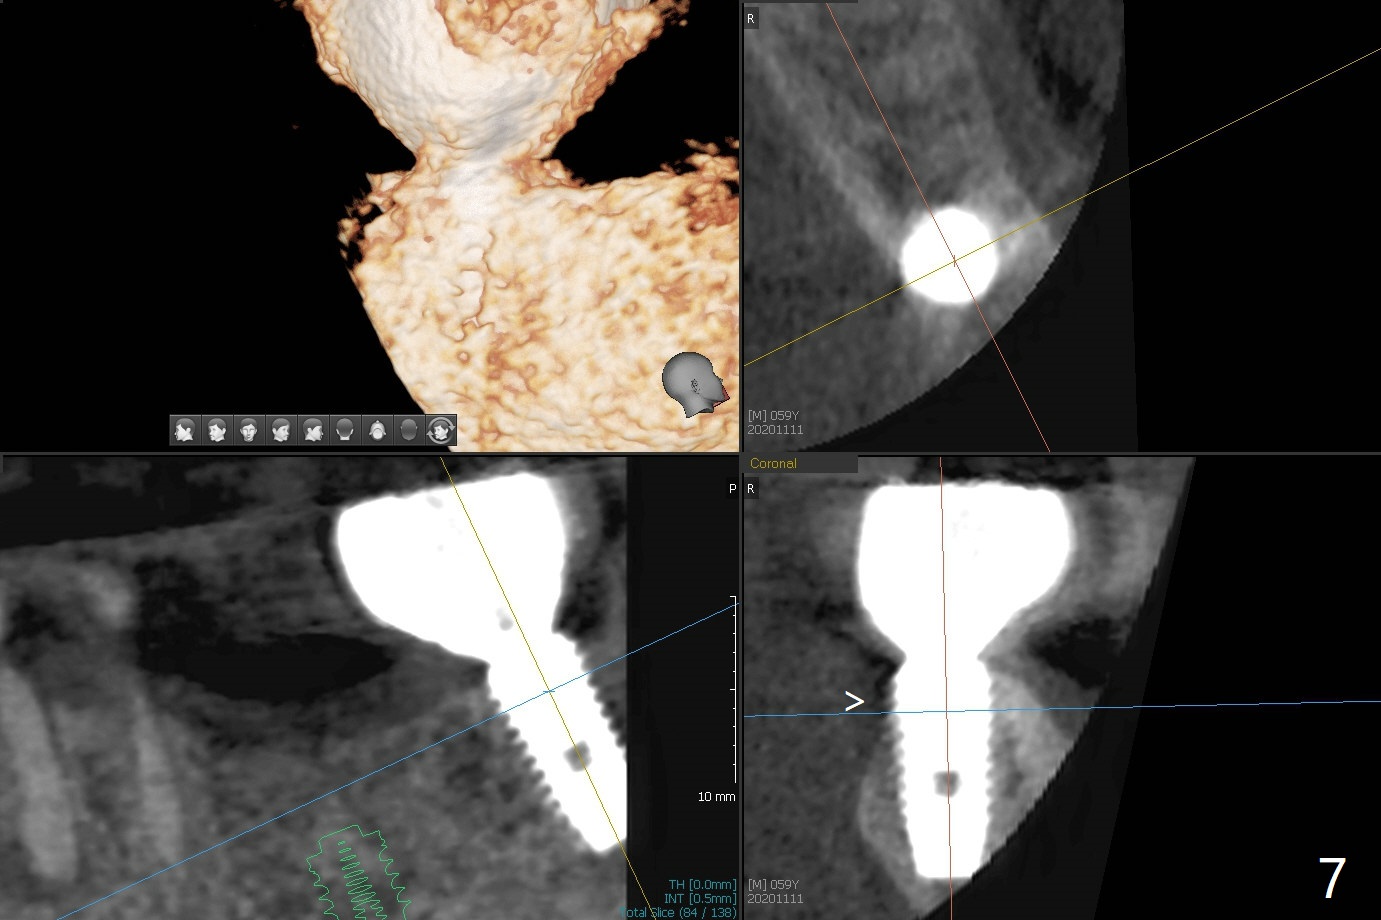

A 58-year-old man requests extraction of the tooth #19 with supraocclusion (Fig.1). After extraction, the septal gingiva has to be sectioned to remove underlying granulation tissue thoroughly. The buccal plate is missing. Ossogen (allograft, Fig.2 *) is placed around the septum (red dashed line). The socket opening is covered by BioXclude and approximated with 4-0 PGA suture, followed by periodontal dressing. With the septum's support, bone graft is expected to heal without too much ridge collapse. The mesial and distal sockets behave as 2 small premolar ones, getting ample blood supply. The socket heals in 20 days (Fig.3). The sockets heal with preservation of the septum (Fig.4: S), while there is formation of the cortical plate on the top of the ridge 10 months postop (Fig.5: ^). It is safe to place a 5x10 mm implant with guide (Fig.6), whereas it may be necessary to place bone graft lingual to the implant at #18 associated with free hand surgery (Fig.7: >). Return to Lower Molar Immediate Implant, No Deviation 18 种植 位点保存 Xin Wei, DDS, PhD, MS 1st edition 01/22/2020, last revision 07/03/2021